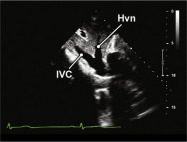

| 2.26. Mặt cắt dưới sườn ghi hình tĩnh mạch gan (video 67) |

||||||||

|

|

Cửa sổ siêu âm dưới sườn

Từ mặt cắt tĩnh mạch chủ dưới, nghiêng nhẹ đầu dò sang phải và ngả đầu dò lên trên. |

Tĩnh mạch chủ dưới (IVC) và tĩnh mạch gan (Hvn) | |||||